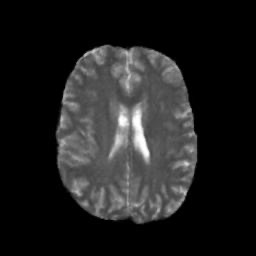

Denoising diffusion probabilistic models (DDPMs) have achieved unprecedented success in computer vision. However, they remain underutilized in medical imaging, a field crucial for disease diagnosis and treatment planning. This is primarily due to the high computational cost associated with (1) the use of large number of time steps (e.g., 1,000) in diffusion processes and (2) the increased dimensionality of medical images, which are often 3D or 4D. Training a diffusion model on medical images typically takes days to weeks, while sampling each image volume takes minutes to hours. To address this challenge, we introduce Fast-DDPM, a simple yet effective approach capable of improving training speed, sampling speed, and generation quality simultaneously. Unlike DDPM, which trains the image denoiser across 1,000 time steps, Fast-DDPM trains and samples using only 10 time steps. The key to our method lies in aligning the training and sampling procedures. We introduced two efficient noise schedulers with 10 time steps: one with uniform time step sampling and another with non-uniform sampling. We evaluated Fast-DDPM across three medical image-to-image generation tasks: multi-image super-resolution, image denoising, and image-to-image translation. Fast-DDPM outperformed DDPM and current state-of-the-art methods based on convolutional networks and generative adversarial networks in all tasks. Additionally, Fast-DDPM reduced training time by a factor of 5 and sampling time by a factor of 100 compared to DDPM. Our code is publicly available at: https://github.com/mirthAI/Fast-DDPM.